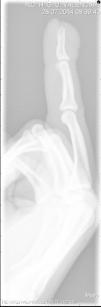

Previamente a la cirugía se realizó una radiografía simple que mostró un nódulo dependiente de partes blandas, sin afectación ósea (fig. 3).